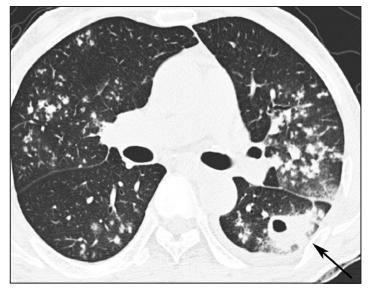

其中,胸部X线(或CT)在诊断PTB具有重要的临床价值。据循证依据,PTB患者感染灶好发于肺上叶尖后段、下叶背段及后基底段,其胸部X线(或CT)可见浸润、干酪样纤维钙化灶或空洞。典型的PTB病例如图1[8]所示。

图1 PTB病例值得注意的是,支气管内膜结核(EBTB)属于特殊的PTB,且10%-20%的EBTB者胸部X线无明显异常(见图2)[9],容易出现结核病漏诊。